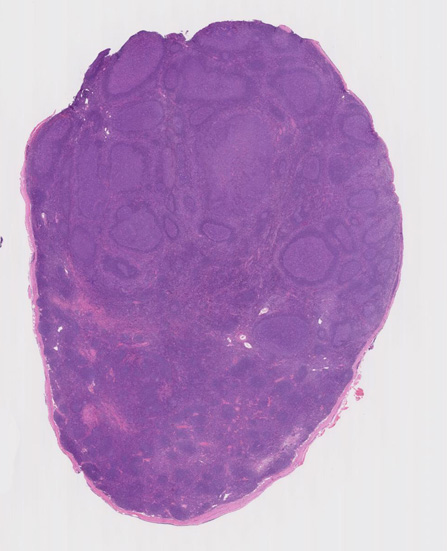

不整形の胚中心(CD20+, CD10+, BCL2-)のまわりにはCD5陽性リンパ球が多く存在してマントル層を形成している. (IgD染色でもマントル層はよく認識できる). 胚中心内のCD5+ cellはfollicular helper T-cellのようです.

大きな胚中心を持つ多数のリンパ濾胞が見られる。胚中心の辺縁は不明瞭でマントル層も薄くなっている。1カ所マントル層リンパ球の侵入によりバラバラになった巨大な胚中心が認められ, macrofollicular patternと記載されるPTGCです。

鑑別にあがるfollicular lymphoma floral variantは全ての濾胞が腫瘍性であり, 本症例では除外可能と考える。

Diagnosis: Reactive lymphadenitis with PTGC